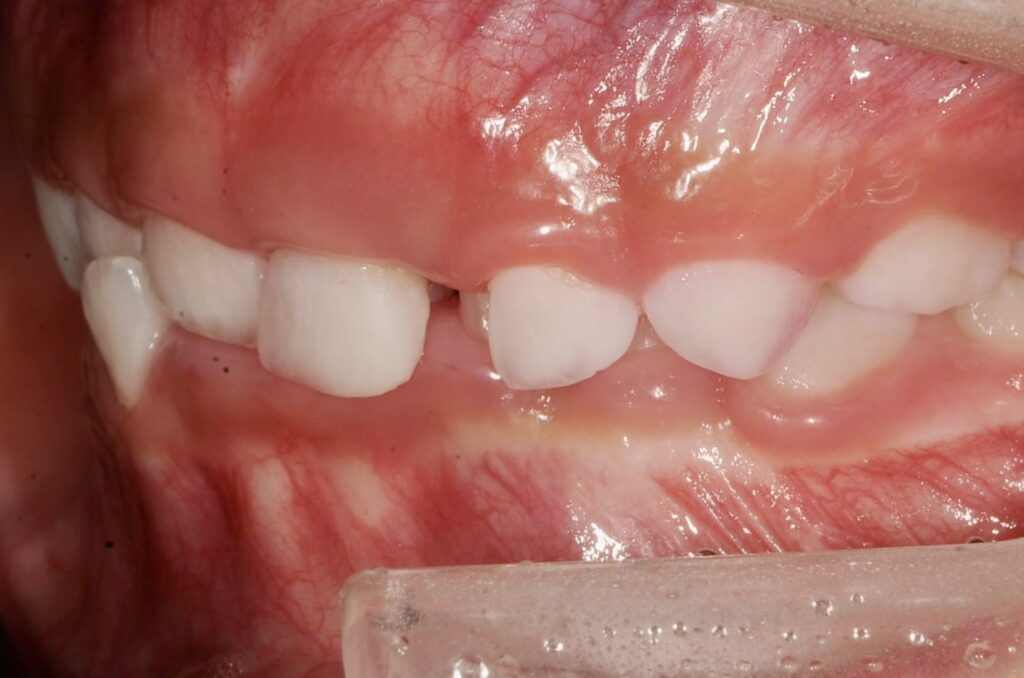

BEFORE

診断名・主な症状

過蓋咬合

治療内容

上下の歯並びの幅を拡げつつ、前歯の関係を改善しました。

使用装置

急速拡大装置

リンガルアーチ

機能的矯正装置(マイオブレース)

抜歯部位

抜歯なし

治療期間

2年 + 後戻り止め期間(5年)

通院回数

25回

費用

50万円程度(税別)

リスク・副作用

痛み、歯肉退縮、歯根吸収、抜歯に伴う出血や腫れが生じることがあります。